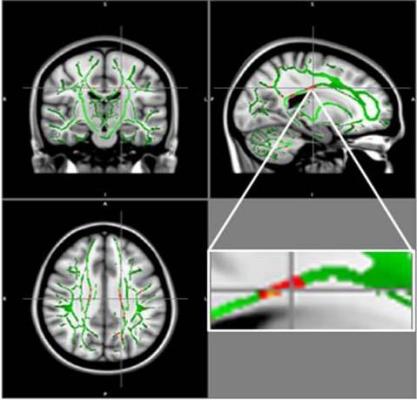

Reduction in fractional anisotropy (FA) in obese patients compared to the control group: At the intersection of the alignment vectors, a large cluster of FA decrease located in the corpus callosum on the left. In red: Reduction of FA in obese patients compared to controls, and FA skeleton (green), superimposed on the mean of FA images in sample. Image courtesy of Pamela Bertolazzi, Ph.D., and RSNA.

For the new study, researchers compared DTI results in 59 obese adolescents and 61 healthy adolescents, ages 12 to 16 years. From DTI, the researchers derived a measure called fractional anisotropy (FA), which correlates with the condition of the brain's white matter. A reduction in FA is indicative of increasing damage in the white matter.

The results showed a reduction of FA values in the obese adolescents in regions located in the corpus callosum, a bundle of nerve fibers that connects the left and right hemispheres of the brain. Decrease of FA was also found in the middle orbitofrontal gyrus, a brain region related to emotional control and the reward circuit. None of the brain regions in obese patients had increased FA.